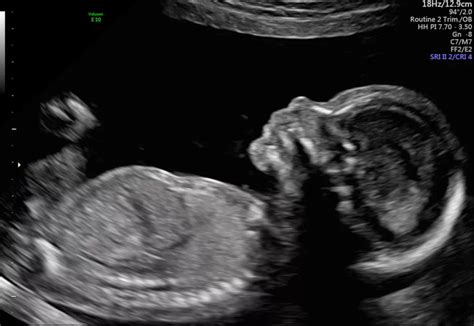

Going through a 20-week scan is a big milestone in your pregnancy. It’s where your healthcare providers take a really close look at your baby. It helps them check everything from the baby’s heart, brain, and spine, to making sure the baby’s kidneys and other organs are developing as they should. You’ll get to see your baby on the screen, watch them move, and perhaps even find out if you’re having a little boy or girl. This scan is when healthcare professionals look for potential problems. If they do find something like IIOSCHOWSC , it’s usually not a time to panic, but rather a prompt for further investigation. Getting this information can be overwhelming, because you might not know what it means. It’s totally okay to feel a mix of emotions – worry, confusion, and even fear. But remember, the healthcare team is there to help guide you through the next steps. They will likely schedule follow-up appointments, which may include more detailed ultrasounds or other tests. The goal is always to get a clearer picture of what’s going on and decide on the best course of action. This might involve additional monitoring during your pregnancy or planning for specific care after your baby is born. During this time, you have the right to ask questions, voice your concerns, and seek support from your loved ones.